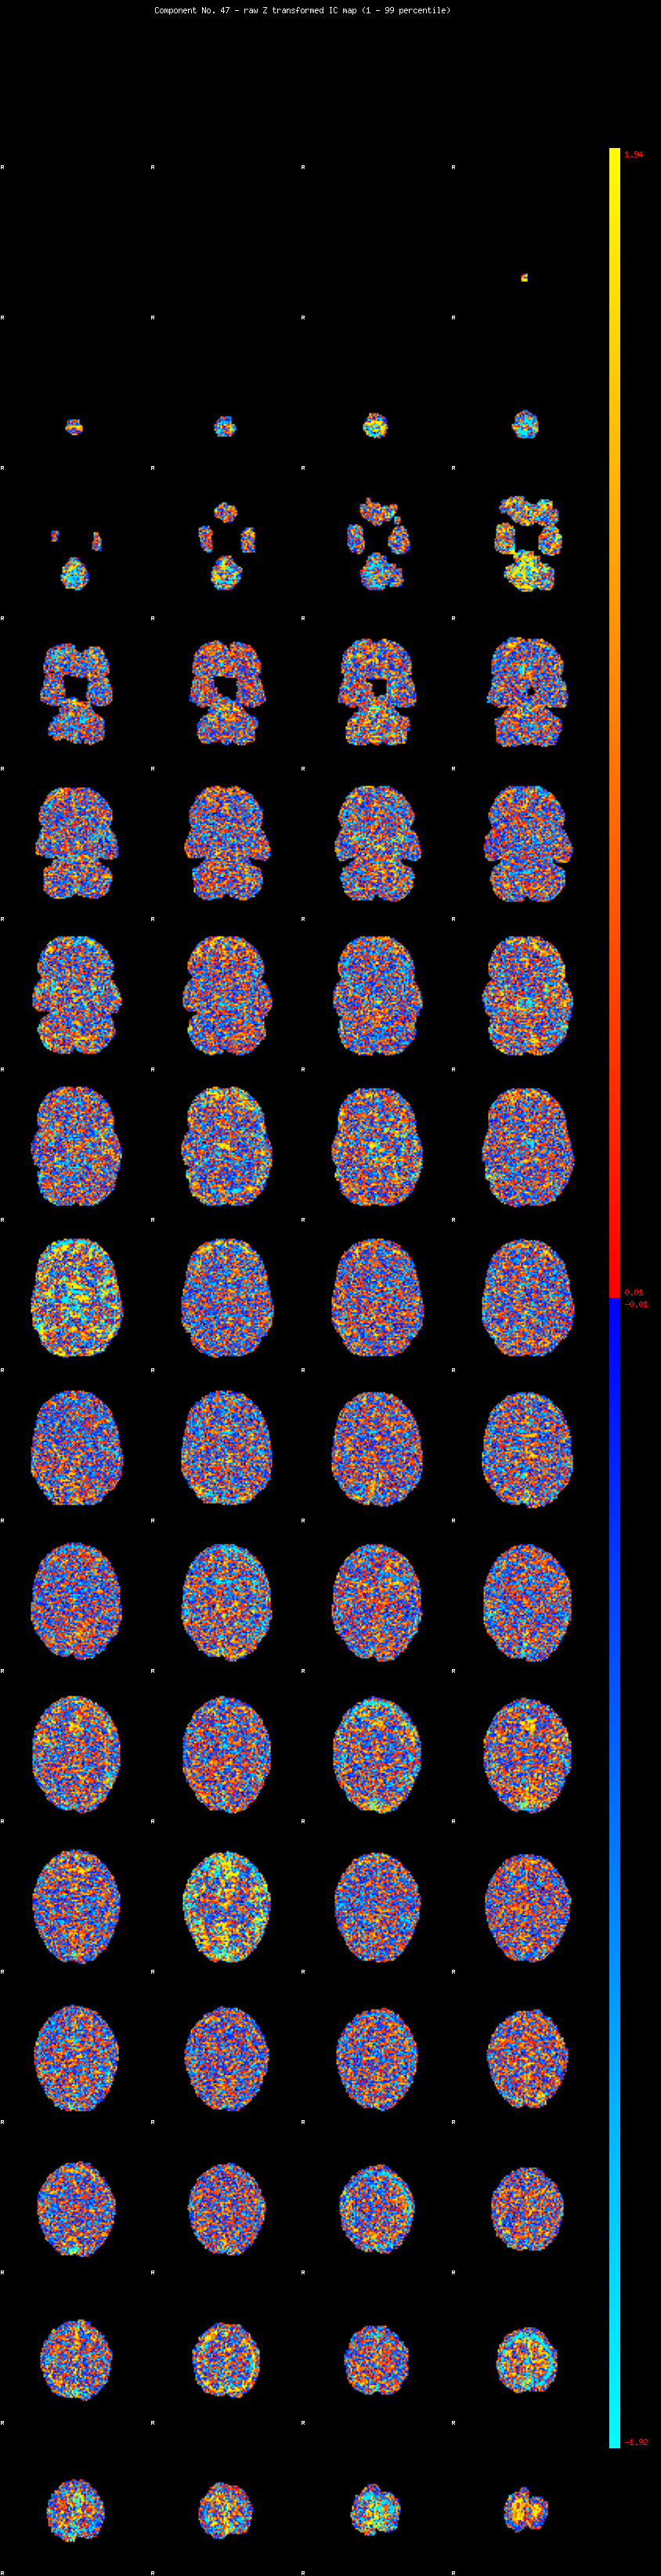

IC_47 Mixture Model fit

Means : -0.000000 2.661223 -2.345617

Vars : 1.000000 2.683451 1.629799

Prop. : 0.948770 0.024354 0.026876